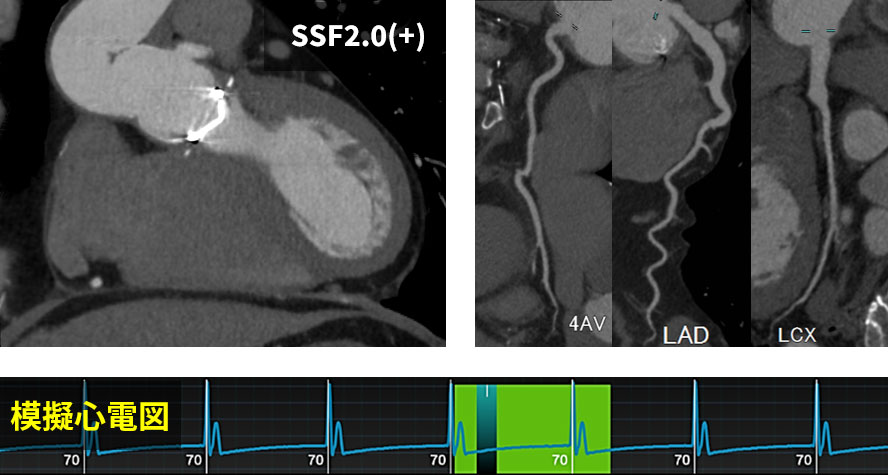

GEHC CTには心臓撮影後のモーション抑制技術として、動態ベクトル解析を用いたモーション抑制アルゴリズム「SnapShot Freeze 2.0」(以下SSF2.0)があります。SSF2.0では、ターゲット心位相とその前後の心位相、合計3つの心位相のデータを用いて、心臓を構成する各ボクセルの動態を3次元的にベクトル解析し、変化量をフィードバックして静止画像を生成します。これに0.23秒ローテーションを組み合わせることで、より高精度な静止画像が取得可能となりました。

当院では、心拍に依存せず、多くの症例でβブロッカーを使用せずに撮影を行っています。その効果として患者様がCT室に滞在する時間が5分以上短縮することができています。また、以前のCTでは、モーションアーチファクトにより評価が困難である症例では、しばしばCAGによる精査が必要でしたが、0.23秒ローテーションとの併用により、ほぼすべての症例でモーションアーチファクトがない画像が得られ、不必要なCAGを減少させることができました(図6、7)。

RevolutionApexElite_Minaminojunkanki08.jpg

(図6)

・平均心拍数107bpm、不整脈(+)、息止め困難の症例

SSF2.0処理を施した結果、

冠動脈および心筋のモーションアーチファクトが補正された。

RevolutionApexElite_Minaminojunkanki09.jpg

(図7)

・Bentall術+上行置換術後、背部痛の症例

単純CT施行後、下行大動脈に新たな解離所見が認められた。

全身のHelical scanによる造影検査を行う前に、上行大動脈も含めて評価するため、

模擬心電図を用いてAxial Scanを追加した。

これにより、上行大動脈や冠動脈の評価も可能となった。